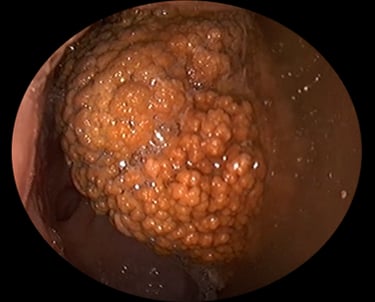

Voor een maagonderzoek (gastroscopie) dient uw paard minimaal 12 uur nuchter te zijn. Na het toedienen van een lichte sedatie voeren we met een camera een inspectie uit van de maag en het begin van de dunne darm.